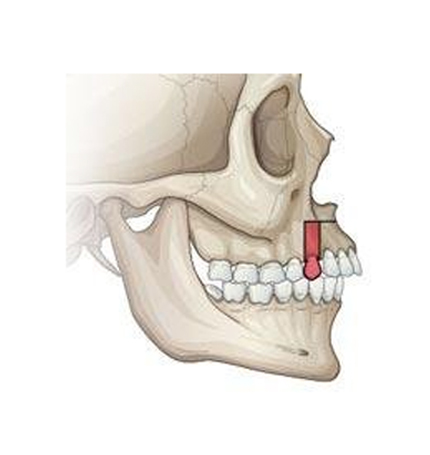

��ǻ���� TEETH